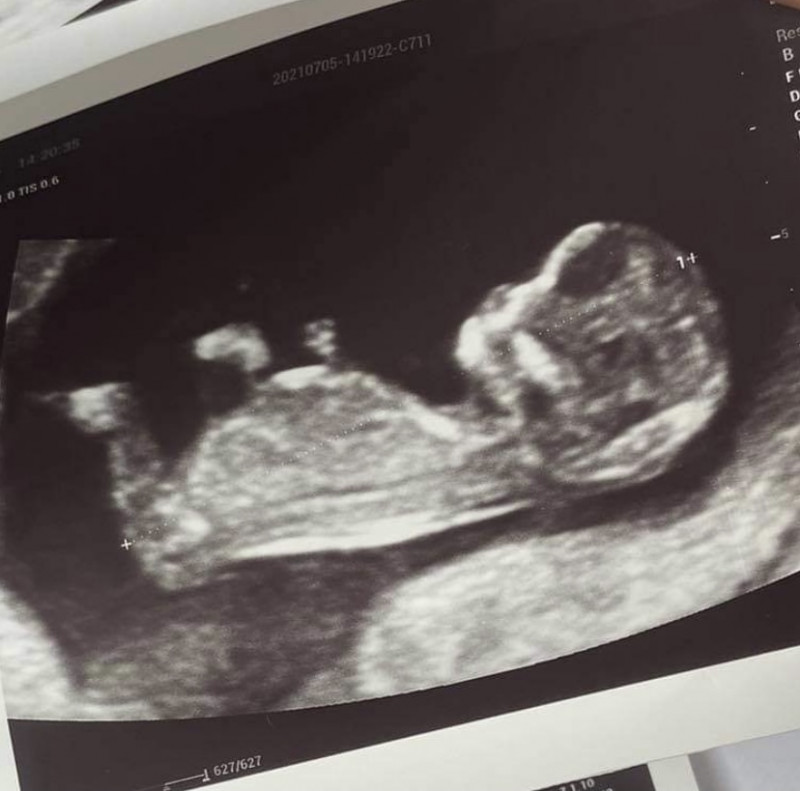

Ikeliu ir as savo, gal turi gera aki. 12 sav irgi 😀

Berniukas 🤔

tai spėju galbūt mergaičiukė 😂

tik dvi turiu, cia kaip tik matosi ta balta linija, kitoj nesimato

Jūs, spėju, mergaitę nešiojate 🙂

hmmm, bandau spet uz mergaite![]()

Nesimato reikiamų kūno dalių, bet iš kaukolės spėju, kad berniukas